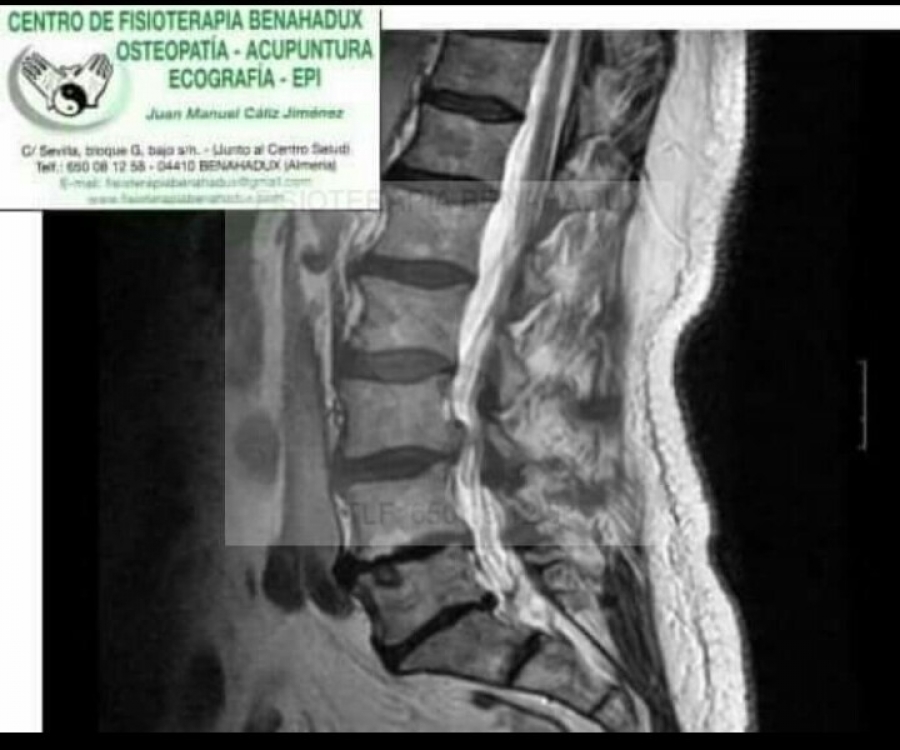

ESTENOSIS FORAMINAL

La columna vertebral tiene diferentes funciones la de sostén pero también la de proteger el sistema nervioso. A través de las vértebras pasa la medula espinal y de ahí salen los nervios que van a recorrer todo el cuerpo, dando inervación a las diferentes estructuras. Estos espacios por los que pasa el sistema nervioso tienen que ser de un determinado diámetro para permitir su correcto paso y movilidad . La estenosis de canal es la reducción de estos espacios y por ello pueden llegar a comprimir estas estructuras nerviosas.